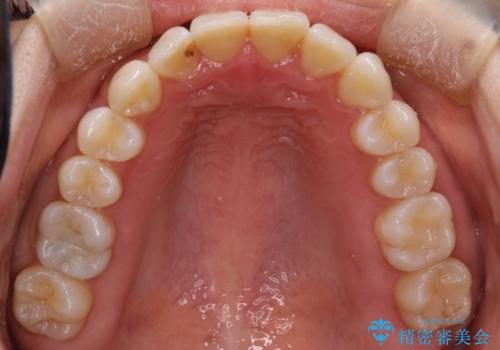

インビザラインによる矯正治療 前歯を整った歯並びへ

患者様に考えていただき、矯正治療で前歯をきれいにすることとしました。

インビザラインを使用して矯正することとしました。